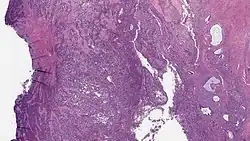

Micrograph of a low-grade endometrial stromal sarcoma. H&E stain. | |

Low-grade endometrial stromal sarcoma consists of cells resembling normal proliferative phase endometrium, but with infiltration or vascular invasion. These behave less[3] aggressively, sometimes metastasizing, with cancer stage the best predictor of survival. The cells express estrogen/progesterone-receptors.